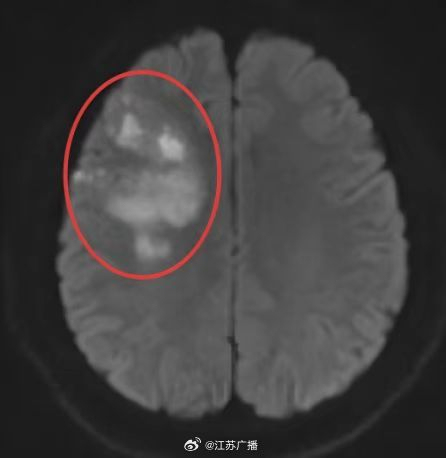

小潘今年29岁,平时饮食不节制且缺乏运动,还有吸烟的习惯,体重达到了115公斤。最近,他在早晨起床时突然感到头痛、视物模糊和口角歪斜。经过医院检查后发现,他患上了多发急性脑梗死

29岁230斤小伙一觉醒来突发脑梗肥胖与不良习惯埋下隐患!小潘今年29岁,平时饮食不节制且缺乏运动,还有吸烟的习惯,体重达到了115公斤。最近,他在早晨起床时突然感到头痛、视物模糊和口角歪斜。经过医院检查后发现,他患上了多发急性脑梗死。

长期肥胖、高血压以及吸烟导致了小潘脑血管动脉硬化和狭窄,而夜间严重的睡眠呼吸暂停和低氧血症缺氧进一步诱发了他的脑血管疾病。